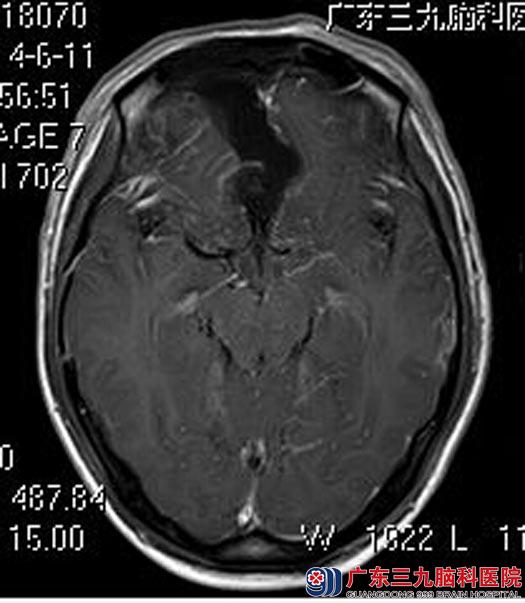

鲁明主任建议手术切除。经家属同意后,由鲁主任主刀,在全麻下行前颅窝底脑膜瘤切除术,术中显微镜下见一质地较中的肿瘤,血供一般,镜下分块切除肿瘤,手术顺利。术后林先生头晕症状好转,康复出院。术后病理结果:过渡型脑膜瘤。

手术后